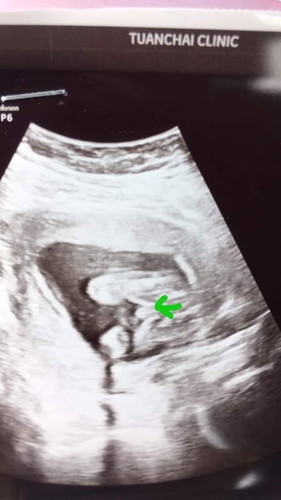

ของเราก็แบบนี้ค่ะหมอบอกผชค่ะอิแม่นี่ขำอิพ่อเลยพูดคำไหนก็ลูกสาวพอไปชาวจู๋ชัดมากอิพี่ขำไม่ออกเลย

น้องเป็นผช.คะแม่ บ้านนี้อยากได้ลูกสาว ตอนไปซาวน์หมอบอกผช. คลอดออกมาก็ผช.คะ 👼👶

แม่อยากได้น้องผญ แต่พ่ออยากได้ผช สรุปผลออกมาได้ผชจร้าจู๋ยาวมาก55

ของเค้าแบบนี้ หมอบอกได้ ญ อะคะ แต่แม่ก้กลัวแอบมีไข่ตอนคลอด😂 20+1 w

น่าจะ ช นะแม่ เหมือนของเราเลย ถ้า ญ จะเป็นกลีบๆ (ท้องแรกลูกสาว)

โด่มาขนาดนี้คงไม่มีโอกาสเป็นผู้หญิงแล้วล่ะคะแม่

เพศชายค่ะแม่ถ้าเป็นเพศหญิงจะไม่มีอะไรนูนออกมา

ชายชัวร์ค่ะ ตอบจากประสบการณ์จิงเลยค่ะ555

จู๋เป็นแท่งขนาดนี้คงเปลี่ยนยากค่ะแม่5555

อันนี้น่าจะผช. ของเรา ผญ. เป็นร่องเลยค่ะ